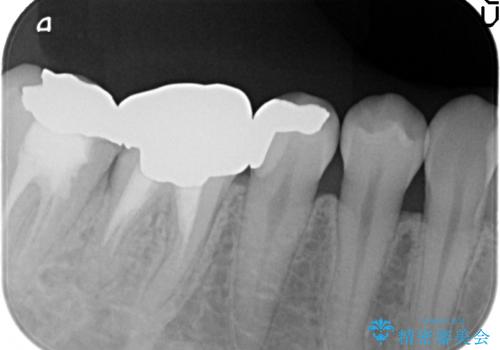

銀歯及び虫歯を除去し、適合に優れたPGA(ゴールド)インレーにて修復を行いました。

ゴールドは化学的な安定性が高いため変色や腐食がほとんどなく、アレルギーなども起こりにくい人体に優しい素材です。

また硬さも天然歯に近いため周囲の歯への影響も少なく、さらに適合もよいため虫歯の再発も少ない、とても補綴に適した材料です。